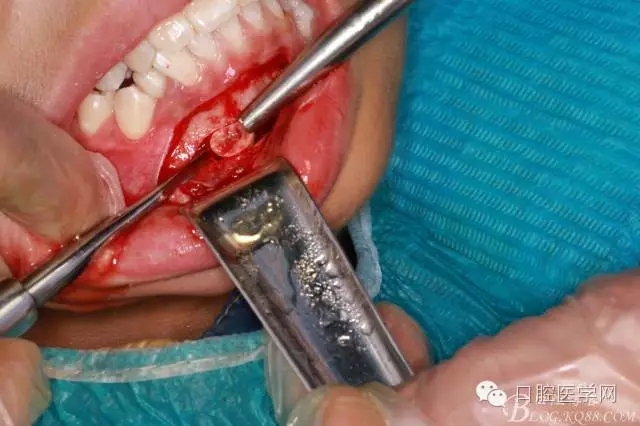

橫位埋伏3的取出術(shù)